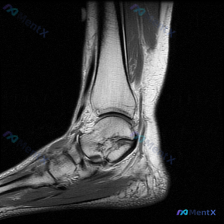

这是踝关节MRI T2加权轴位图像,扫描层面为踝关节远端,可见距骨体及周围软组织结构,图像对比度满足观察要求,T2加权像液体呈高信号。

- 骨结构:距骨及周围骨性结构骨髓无异常高信号,骨皮质完整,无明确骨质破坏或骨折线

- 关节与软组织:距骨周围关节间隙可见高信号液体影,提示踝关节积液;踝关节外侧及前外侧软组织存在弥漫性T2高信号,提示局部软组织水肿渗出

- 韧带结构:外踝周围软组织高信号,距腓前韧带区域信号增高、增粗,连续性欠佳、走行模糊

- 肌腱腱鞘:腓骨长短肌腱腱鞘周围可见环形新月形高信号积液影,肌腱本身信号稍增高;内侧胫骨后肌腱区域未见明显异常

整理下来核心发现就是三个:踝关节外侧韧带复合体区域异常信号伴水肿、腓骨肌腱鞘中度积液、踝关节少量至中量关节积液。